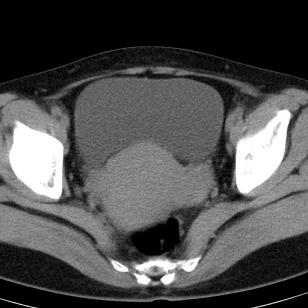

标题: CT19559:子宫及附件正常吗?

女,35岁,反复下腹部隐痛数月。

感觉上,子宫好象大了点

如果未孕,子宫体稍大,宫腔增宽,附件区未见异常密度影,还是建议结合b超检查为好,ct平扫对妇科没有优势。

子宫弥漫性等密度肿大,宫腔内缘见结节影突入腔内,子宫内膜异位可能